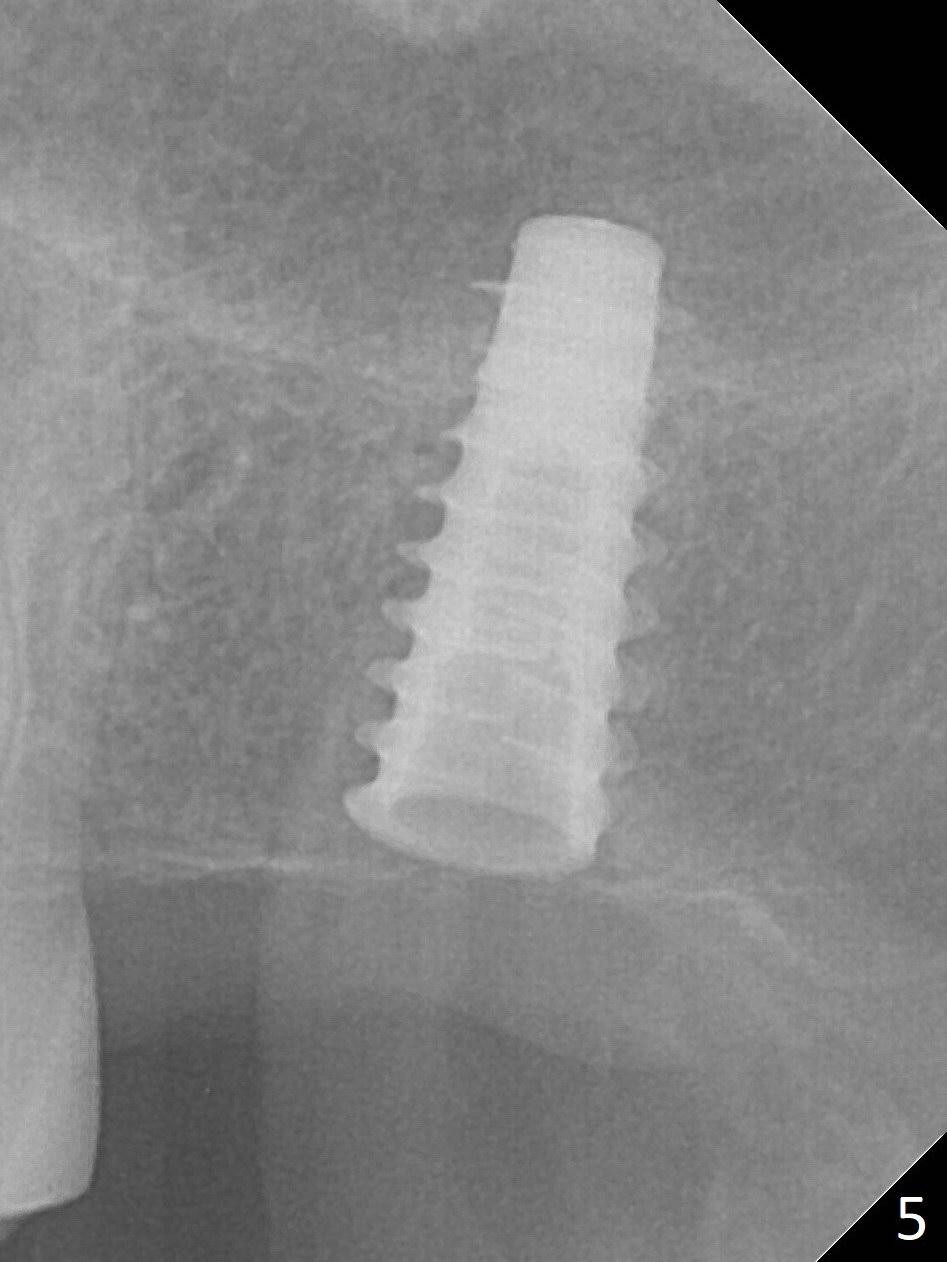

The ridge is pointed at the site of #15 (Fig.1). A 1.2 mm initial drill is used to start osteotomy for 10 mm, followed by an incision over the ridge mesiodistally for ~ 8 mm. After tapping the #15 C blade, the 1st Bone Expander 1.0/1.6 mm) is inserted for ~ 11 mm (Fig.2, 20 Ncm). Bone expansion continues until #4 Expander (2.4/3.7 mm, Fig.3). When 4x11 mm and 4.5x11 mm dummy implants are placed (Fig.4), insertion torque remains 20 Ncm. Following placing allograft with 3-4 amalgam carriers, a 5x11 mm IBS implant is placed with 20 Ncm (Fig.5,6). In fact the implant turns when an abutment is placed. When the implant is re-inserted, torque decreases to 10 Ncm. Instead a healing screw is placed. The low torque value is due to soft bone and failure to underprep. #4 Expander (Fig.3) seems larger than 4.5 mm implant (Fig.4). #3 Expander (1.7/3.1 mm) should have been used prior to definitive implant placement. The implant appears to have osteointegrated 3 months postop (Fig.7); impression is taken. The bone density at the crest increases 1.5 years post cementation (Fig.8 *, as compared to Fig.6), although there is mild bone loss. Implant placement should be deep when bone expansion is carried out. The tooth #14 develops a buccal fistula, corresponding to periapical radiolucency of the mesiobuccal root (Fig.9 white >). The abutment of #15 may be incompletely seated (black <). PA taken when RCT of #14 is finished does not show the incomplete seating of the abutment (Fig.10). Since there appears no history of abutment screw loosening, the abutment is not reseated when #14 is prepared for crown. Recall 3 years 7 months post cementation shows incomplete seating of the abutment (Fig.11 >). After crown proximal reduction (Fig.12 *) and clockwise turn of the crown, the abutment appears to be completely seated. When the case returns from lab, the separate crown and abutment cannot be connected to the fixture because of soft tissue adaptation and change in a month. The abutment is reseated to the fixture analog in the model and the crown is recemented with temp bond (in case of misalignment) while making sure that the crown has the best proximal contact with the neighboring crown. With the abutment and crown in a unit, it is much easier to reseat the abutment with normal proximal contact. The torque is 20 Ncm. The access hole is closed with Cavit.